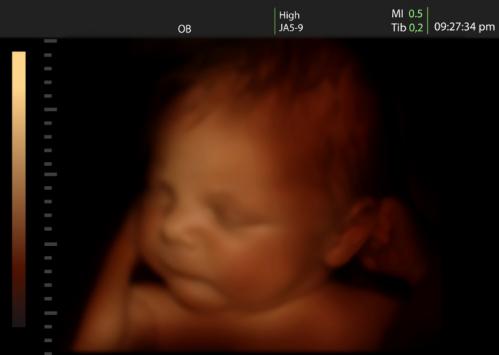

三维超声是这样的:

在超声图像上就能够看到胎儿的一张脸部或者手脚的静态照片